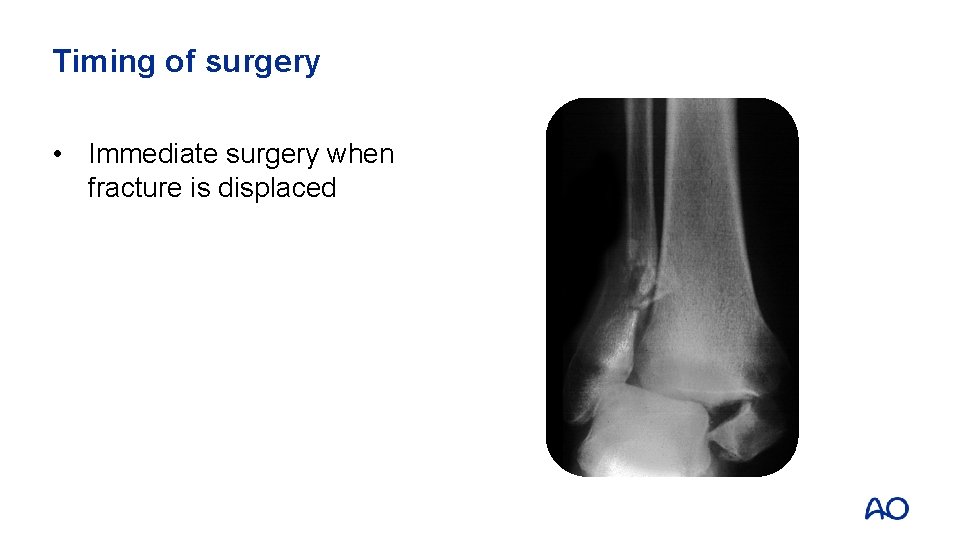

Timing of surgery • Immediate surgery when fracture is displaced

Timing of surgery • • Immediate surgery when displaced fracture Postpone definitive surgery when • Ankle is swollen • Local skin has blisters • Skin looks like orange peel

Timing of surgery • • • Immediate surgery when displaced fracture Postpone definitive surgery Apply external fixator as temporary stabilization